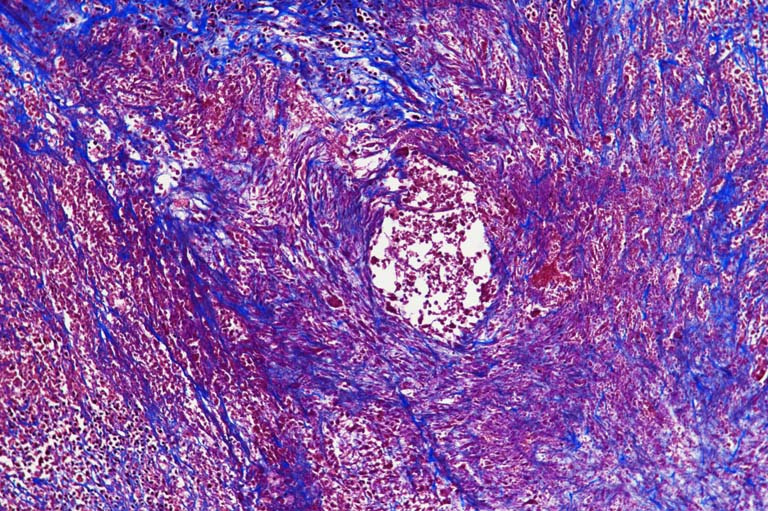

These are images of sections of tumors that have been stained to try and understand what is happening inside the tumor. Using this stain we can tell apart live cells from dead cells and we can see whether the tumor cells have started building up extracellular matrix. In these images you can see how complex the inside of these tumors are--there are pink dense live cells, less dense and more purple dead cells, and there are swaths of blue stained extracellular matrix (specifically collagen). In some of the images the extracellular matrix delineates a border between zones that have dead cells or live cells, whereas in other images, the extracellular matrix completely intertwines with either zone.